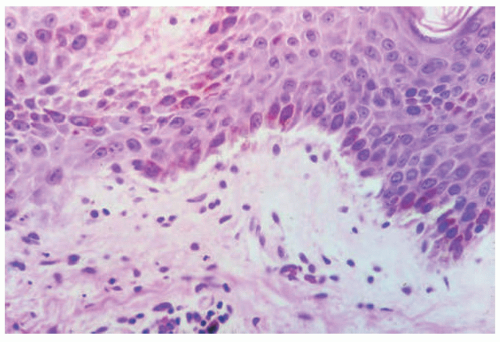

EBS is, by definition, an intraepidermal process, and intraepidermal blister formation is seen histologically (Figure 4-4).6

In the most common basal types of EBS, a split in the epidermis just below the nuclei of the basal layer keratinocytes is most characteristic (Figure 4-4), although superficial layers of the epidermis can become involved with significant trauma.6 Histologic sections for light microscopy may appear to demonstrate a subepidermal blister, as only a small portion of the basal layer keratinocyte cytoplasm may remain attached to the dermis. This is particularly true of older lesions.6 Faint remnants of basal cell keratinocyte cytoplasm are often identified at the base of the blister, and the nucleated half of the split keratinocyte may be found in the blister cavity.6 Blisters are often multiloculated, a feature most commonly seen in early lesions.6 Very early lesions may show only prominent vacuolization (sometimes referred to as “cytolysis”) of the basal layer keratinocyte cytoplasm just below the nucleus6 (Figures 4-4 and 4-5).

DIF or IHC studies show keratin(s), laminin, and type IV collagen along the floor of the blister. The presence of keratin, together with laminin and type IV collage, proves that small portions of the basal layer keratinocytes are present at the floor of the blister, confirming an intraepidermal process.8